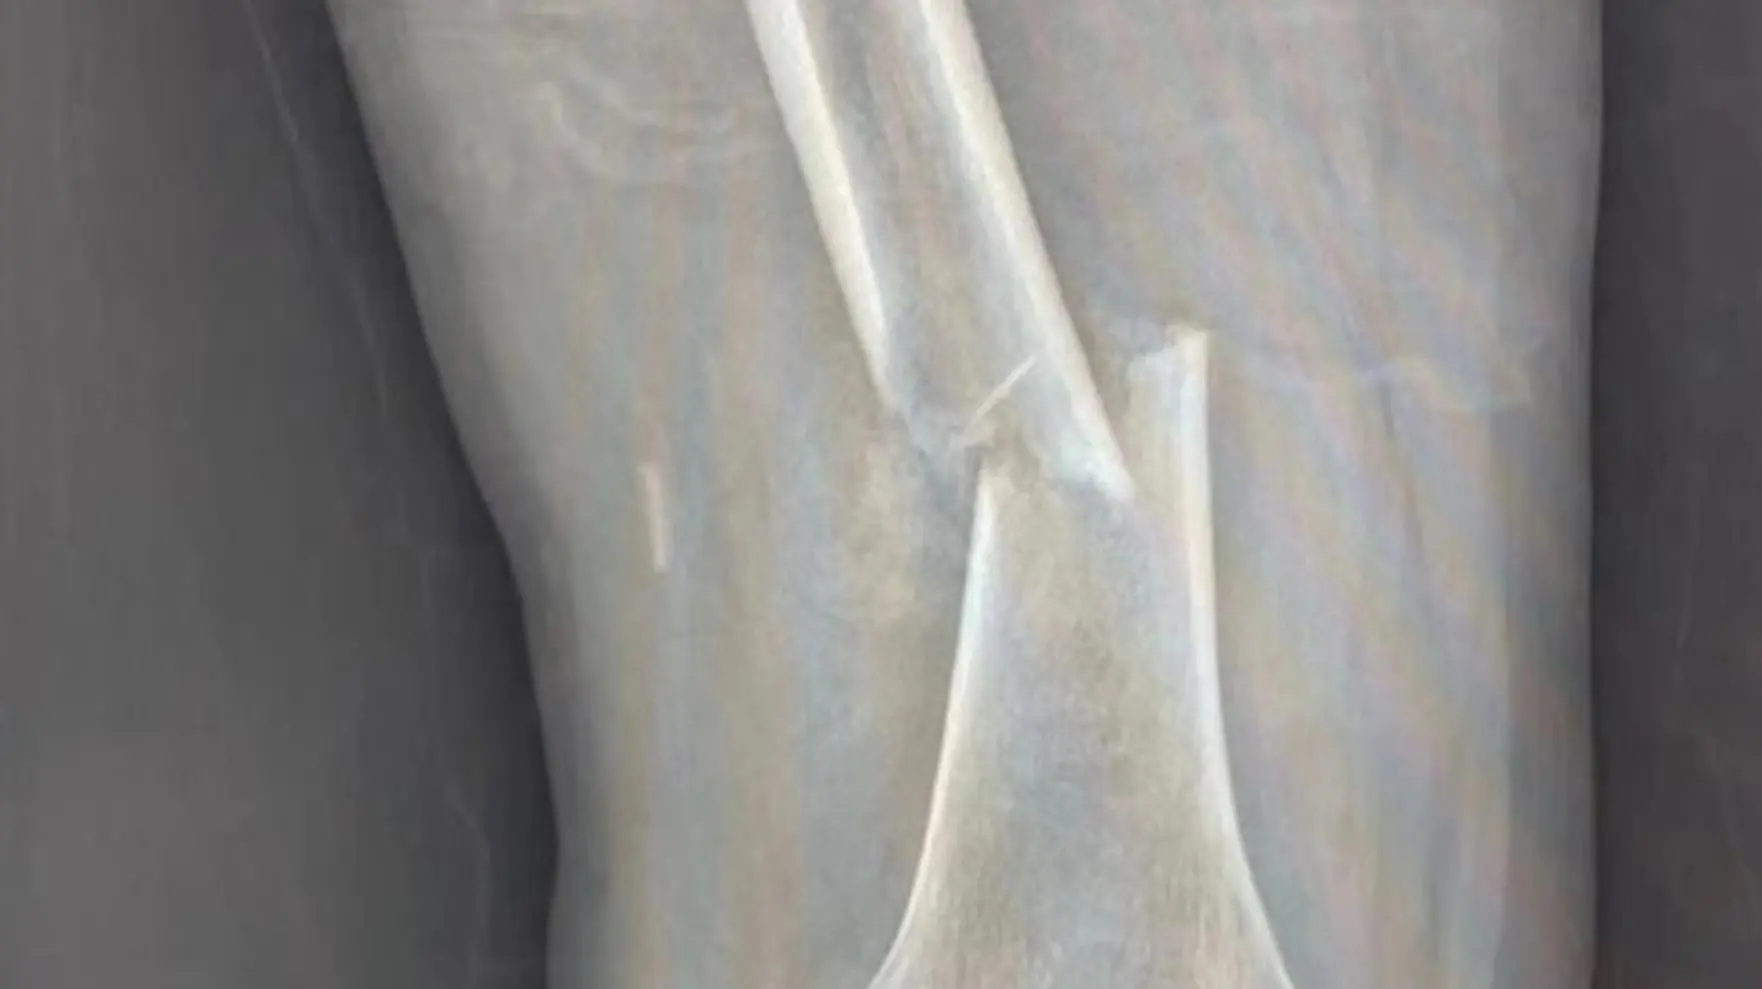

http://res.youth.cn/img-detail/adfc0b7a7c1748b09a5bbbda4d31aef0:1008:643.jpg/webp后来,这种情况越来越严重,张大爷已经无法正常行走了,才让家人安排自己去医院检查,这一检查才发现,张大爷的大腿骨头走断了。

平时要强的张大爷哪里能接受这种情况,就连忙询问医生,说自己身子骨十分硬朗,每天都会走三万步数,基本上都是15公里左右,走了这么多步,自己的骨质肯定非常好,怎么可能断了呢。

http://res.youth.cn/img-detail/4d2f73d4979a3b93cf90c13456abc7a1:1762:989.jpg/webp听到每天步数三万步,医生感到非常震惊,随后告知张大爷走路确实能提高中老年人免疫力以及预防心脏病等作用,但是走路也应该做到科学合理,及时关注自己的身体反馈,过高强度的走路不但达不到预期效果,还可能给身心带来巨大的伤害。